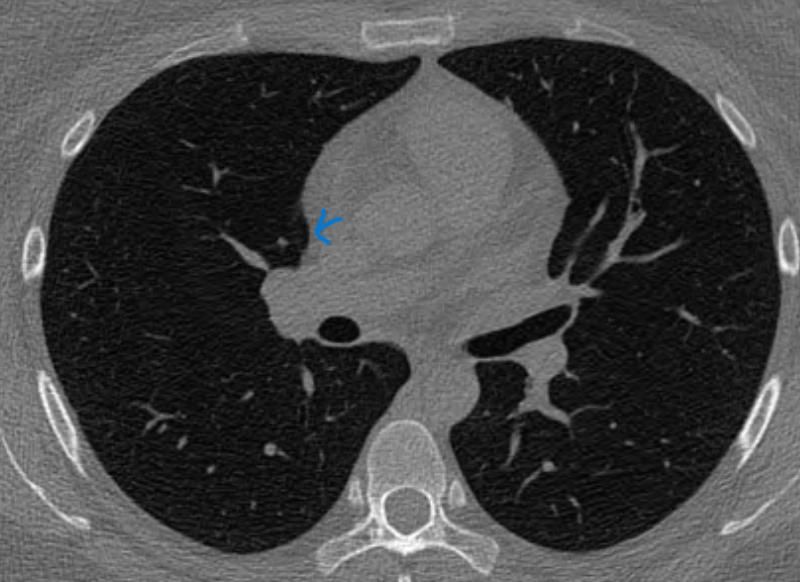

3thk 적힌거 제외 1thk입니다.

의사 두분은 간유리라고 했는데 두번째 병원에서 영상판독지 고형이라고 나왔는데

시리즈를 다른거 보신거 같아요.

ct영상이 목록이 나뉘어 있는데 빨간화살표 표시가 5시리즈 1thk였는데

판독지도 의사분도 2시리즈 3thk 영상기준 설명해준거 같아요. 판독지에 2시리즈 52(사진상 3thk) 라고 적혀있었음.

슬라이드 마다 고형같고 간유리 같고 반고형( 빨간화살표 사진)은데 확인부탁드려요

• 1번 째 사진

• 제시된 CT 단면만으로 확정적인 결론을 내리기는 어렵지만, 영상 형태를 종합하면 전형적인 고형 결절로 보기는 제한이 있습니다. 표시된 병변은 경계가 비교적 또렷한 구조처럼 보이지만, 연속된 슬라이스에서 일정한 덩어리로 유지되는 고형 결절의 특징보다는 인접 구조와 이어지는 양상이 의심됩니다. 특히 슬라이스 두께가 1mm와 3mm에서 다르게 보이고 특정 시리즈에서만 강조되는 점은 부분용적 효과에 의해 고형처럼 보일 가능성을 시사합니다.

간유리 결절은 폐 실질 내에서 흐릿하게 음영이 증가하면서 혈관 구조가 그대로 비쳐 보이는 형태가 특징인데, 현재 영상에서는 그러한 전형적인 간유리 음영보다는 비교적 명확한 구조물 형태로 관찰됩니다. 따라서 간유리 결절로 단정하기도 어렵고, 고형 결절로 보기에도 일관성이 부족한 상태입니다.

오히려 폐혈관이 단면으로 보이거나 혈관과 연속된 구조일 가능성이 더 높습니다. 폐 CT에서는 혈관이 단면에서 원형 또는 타원형으로 보일 수 있고, 촬영 각도나 절편 두께에 따라 결절처럼 오인되는 경우가 흔합니다. 동일 위치에서 1년 전과 이후 CT에서 반복적으로 보이는 경우도 정상 혈관 구조로 설명이 가능합니다.

결론적으로 현재 자료만으로는 고형 결절로 확정하기 어렵고, 간유리 결절의 전형적 소견도 아니며, 혈관 또는 혈관 관련 구조일 가능성이 상대적으로 높습니다. 최종 판단은 1mm 이하 얇은 절편의 연속 영상에서 병변이 독립된 결절 형태로 유지되는지, 혈관과 연결되는지를 확인하는 것이 핵심이며 동일 조건의 CT로 비교 판독을 받는 것이 가장 정확합니다.